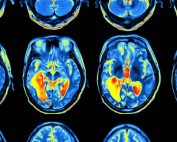

Nuestros cerebros recuerdan las cosas según la forma en que las aprendemos

Investigadores de la Universidad de Oxford han descubierto que el conocimiento aprendido se almacena en [...]